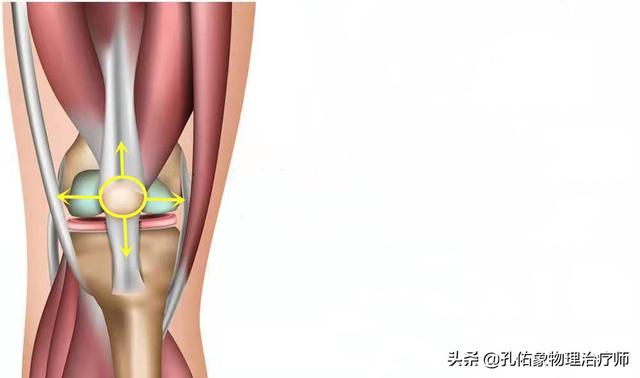

膝を伸ばすと、膝蓋骨は膝関節の屈曲と伸展に伴って動いていることがわかります。膝蓋骨の下には、いわゆる膝蓋下脂肪体があり、膝関節伸展の構造上重要な部分です。膝蓋下脂肪体は、膝関節伸展運動のクッション効果を持ち、膝関節伸展運動を円滑な構造に保つ働きがあります。

一般的に、このような構造は、膝関節を繰り返し使う中で摩耗や損傷を引き起こし、膝関節の動きに何らかの影響を与えることになり、動作時のガタつきはその表れのひとつと考えられる。

また、関節が動くとガタつく原因として、関節面の過度の摩耗というものもあります。 私たちの膝関節は、関節面が滑らかに動くように細かい滑らかな軟骨で覆われているのですが、ケガや使いすぎなどで摩耗が進むと、関節面が凸凹になり、関節が動くときにその凸凹の上を骨が滑ってガタつくのです。関節が動くと、骨が凸凹の関節面を滑ってガタが生じ、激しい痛みを伴います。